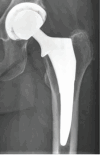

Background: In the United States, cementless fixation is the gold standard for elective total hip arthroplasty (THA). Many modern cementless stem designs have re-introduced collared stem options in recent years which have demonstrated a lower risk of fracture. Minimal studies, however, outline radiographic performance of this novel stem design. As such, the primary purpose of this single-center study was to determine the radiographic performance, including defining patterns of radiographic incorporation and remodeling, associated with this novel, single stem design.

Results: A total of 592 encounters (562 patients) were included in the final analyses. At the one-year postoperative visit, no stems met the criteria for radiographic loosening, 502 (85.2%) patients had distinct radiographic osseointegration of their stem as defined by at least one radiographic spot weld. There was an 18.7% incidence of calcar-collar gaps on initial radiographs and 66.7% of these filled in by one-year. The intraoperative fracture rate was 0.7% without any cases of secondary stem revision or loosening and only 0.8% of stems showed subsidence (i.e., all less than 5 mm) without loosening or revision. Thigh pain within the first year was reported in 1.7% of patients. The all-cause stem revision at one-year was 0.2%.